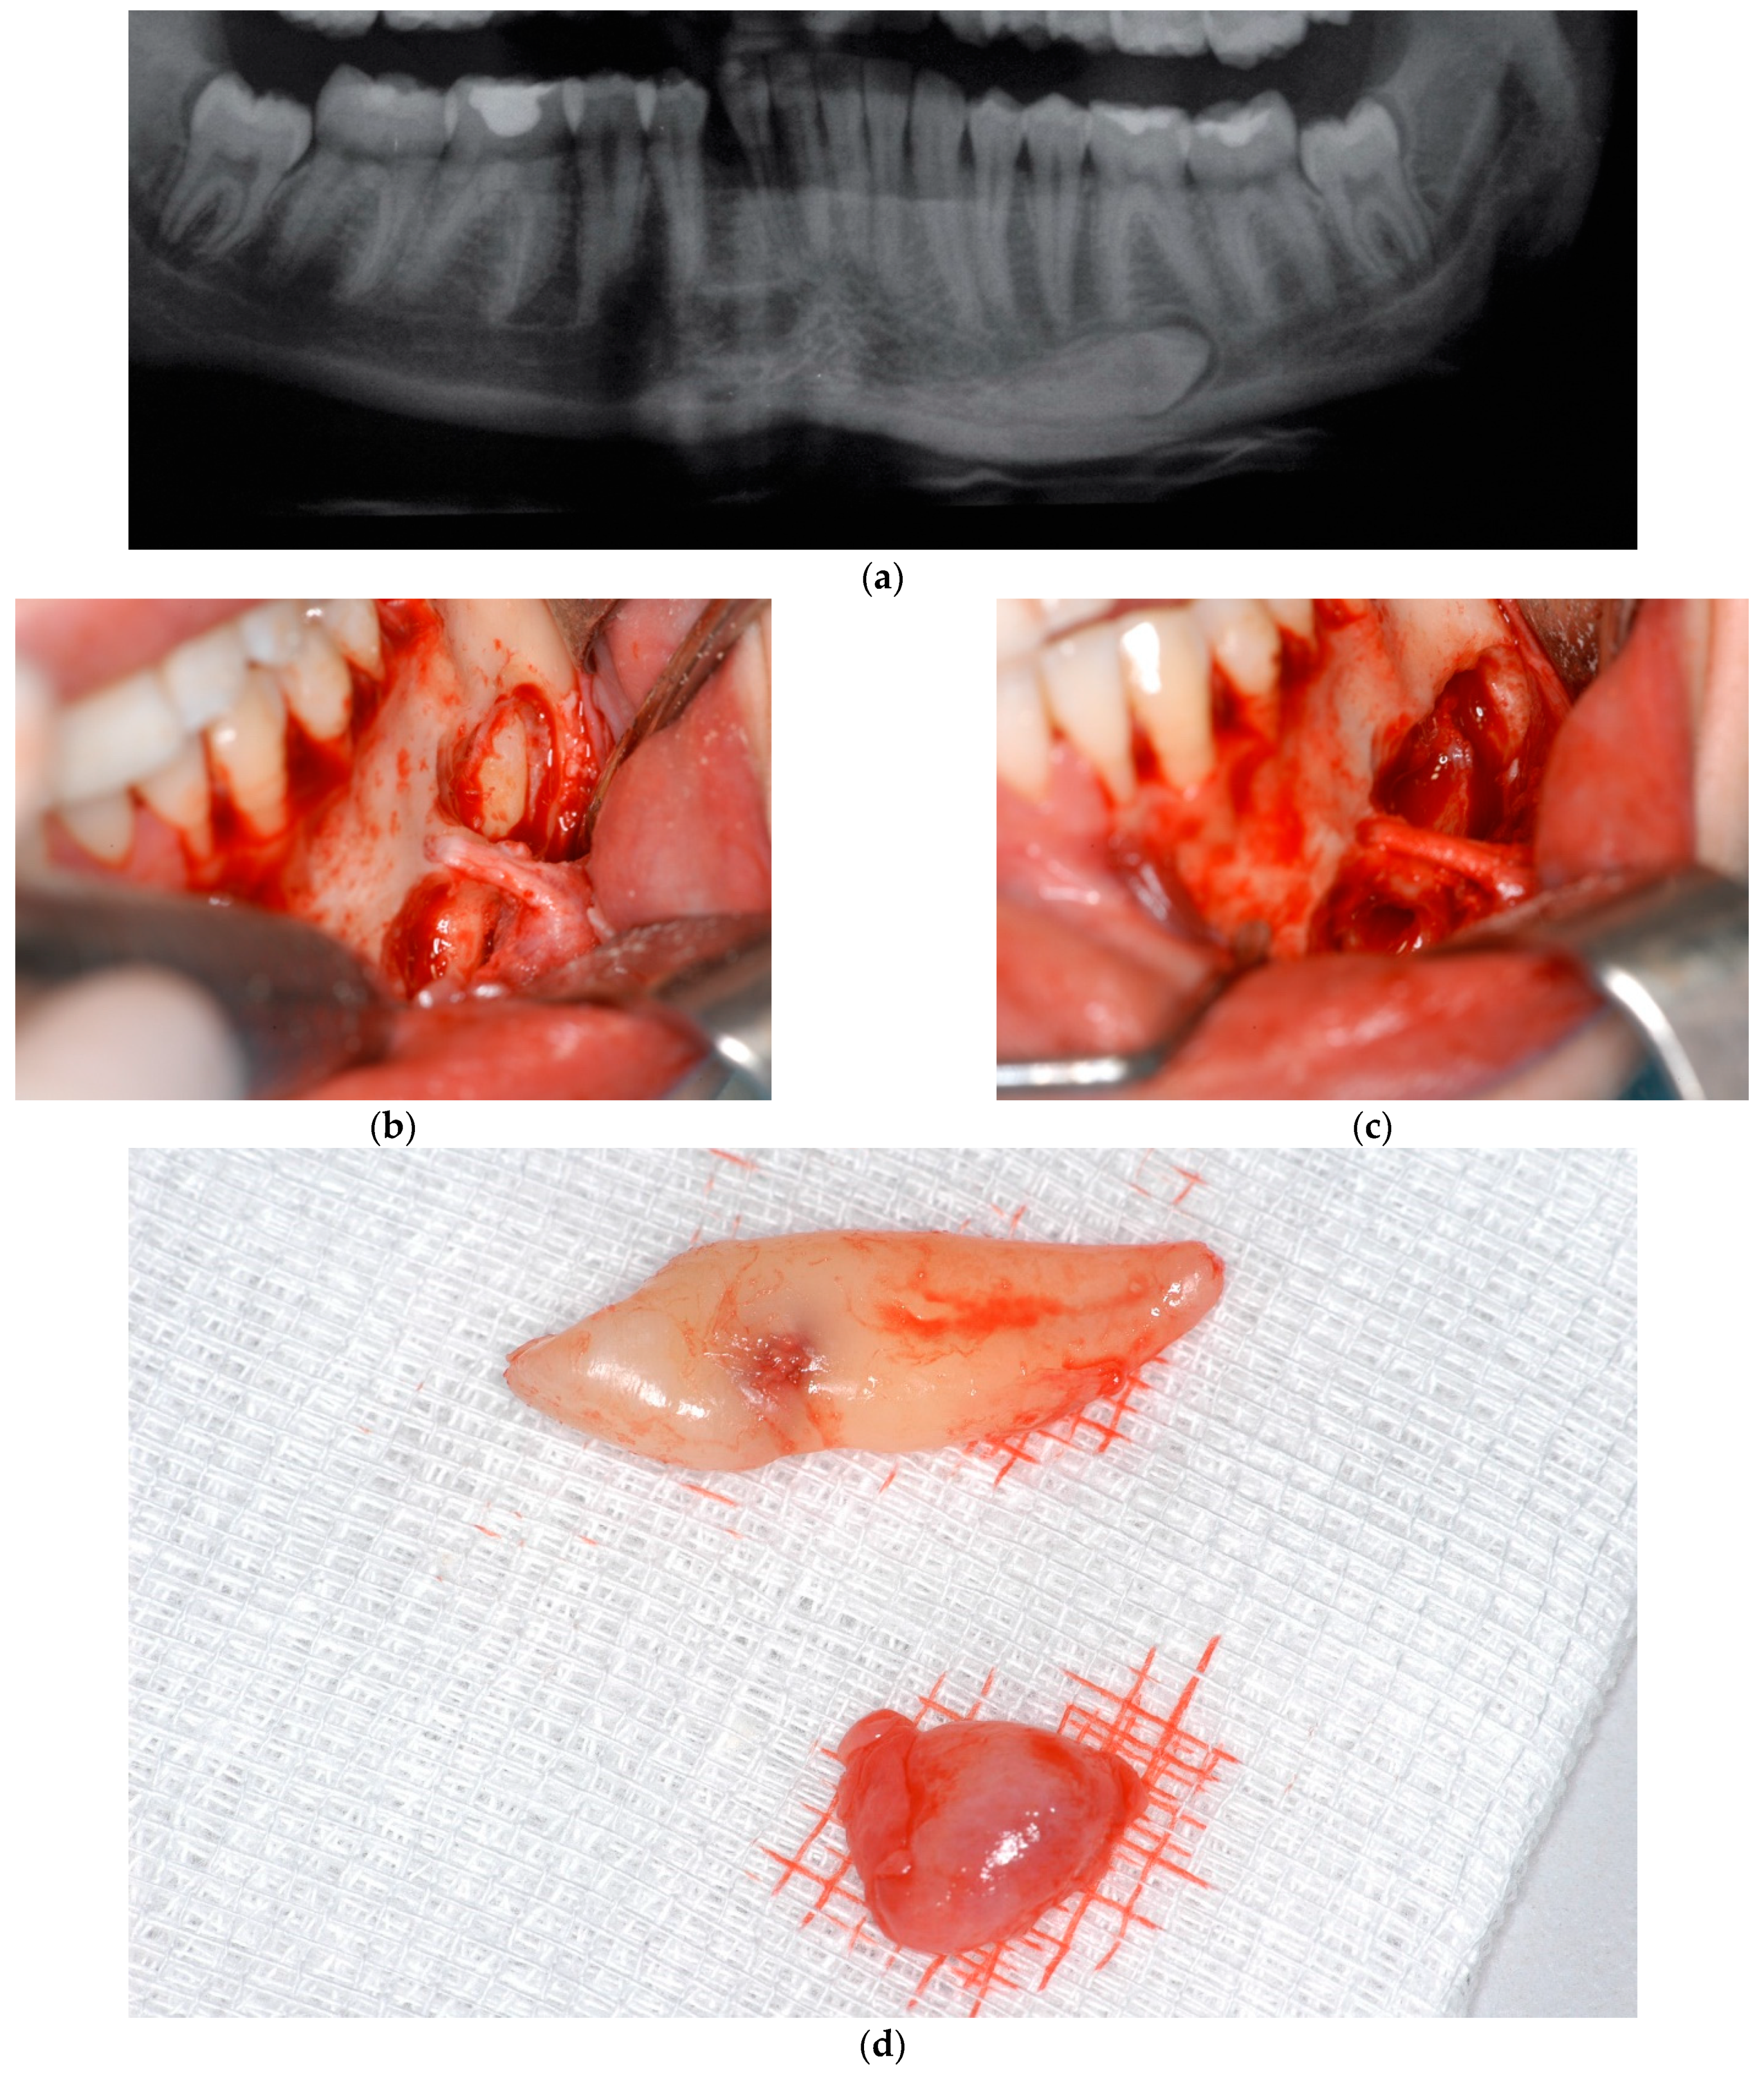

- Herrera-Atoche, J.R.; Esparza-Villalpando, V.; Martínez-Aguilar, V.M.; Carrillo-Ávila, B.A.; Escoffié-Ramírez, M. Treatment options for mandibular canine transmigration—A case series based on dental literature. Br. J. Oral Maxillofac. Surg. 2021, 59, 973–981. [Google Scholar] [CrossRef] [PubMed]

- Sinko, K.; Nemec, S.; Seemann, R.; Eder-Czembirek, C. Clinical Management of Impacted and Transmigrated Lower Canines. J. Oral Maxillofac. Surg. 2016, 74, 2142.e1–2142.e16. [Google Scholar] [CrossRef] [PubMed]